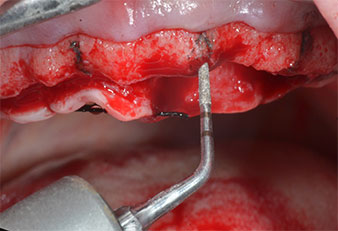

Piezomed I2A/I2P instruments

Fig. 4: The next step is pilot enlargement with the Piezomed I2A/I2P instruments, which are applied in a rotary horizontal movement.